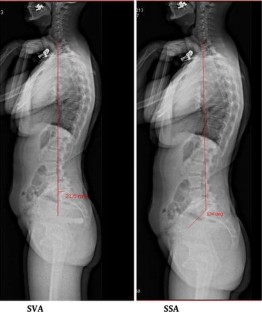

Significant improvement toward more normal values for PT and SS in relation to PI was observed after surgery. Pelvic incidence was unaffected by surgery. Correction of the spinosacral angle shows that the anterior tilt with anterior sagittal imbalance due to spondylolisthesis may be corrected by reduction and fusion of the slipped level. Functional outcome was satisfactory with a statistically significant difference between preoperative values and final follow-up values. The sub-group of patients with insufficient restoration of sagittal balance parameters had less good outcomes than the others.

Surgical management of low- and mid-grade isthmic spondylolisthesis showed good clinical outcome with restoration of correct values for the pelvic position-dependent parameters, i.e., pelvis tilt, sacral slope, C7 plumb line position and SSA.